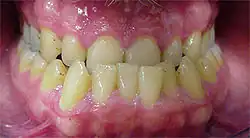

Während bei der echten Progenie äußerlich ein vorstehendes Kinn, ein vorverlagerter Unterkiefer mit kräftiger Unterlippe (positive Lippentreppe) erkennbar sind, ist die unechte Progenie durch ein abgeflachtes Mittelgesicht und eine eingefallene Oberlippe gekennzeichnet. Im Mund ist die Progenie häufig durch einen schmal ausgebildeten Oberkiefer und einen breiten Unterkiefer charakterisiert. Im Oberkiefer kommt es zum ausgeprägten Platzmangel, während im Unterkiefer teilweise Lücken aufgrund eines Platzüberschusses zu beobachten sind. Die Zungenruhelage ist bei den betroffenen Personen meist unten und nach vorne. Häufig weisen sie auch eine Mundatmung auf. In der Okklusion zeigt sich der so genannte Mesialbiss. Nicht selten findet man nicht nur einen umgekehrten frontalen Überbiss, sondern eine vollständige Umfassung des Oberkiefers durch den Unterkiefer. In einer Röntgen-Übersichtsaufnahme (Orthopantomogramm) der Zähne fallen die enge Zahnkeimlage im Oberkiefer und die weite Keimlage im Unterkiefer, insbesondere im Bereich der 2. Prämolaren- und Weisheitszahnkeime, auf. Die Fernröntgenseitenaufnahme des Schädels stellt die Fehlrelation von Ober- und Unterkieferbasis sowie die eventuelle Schneidezahnfehlstellung eindrucksvoll dar.